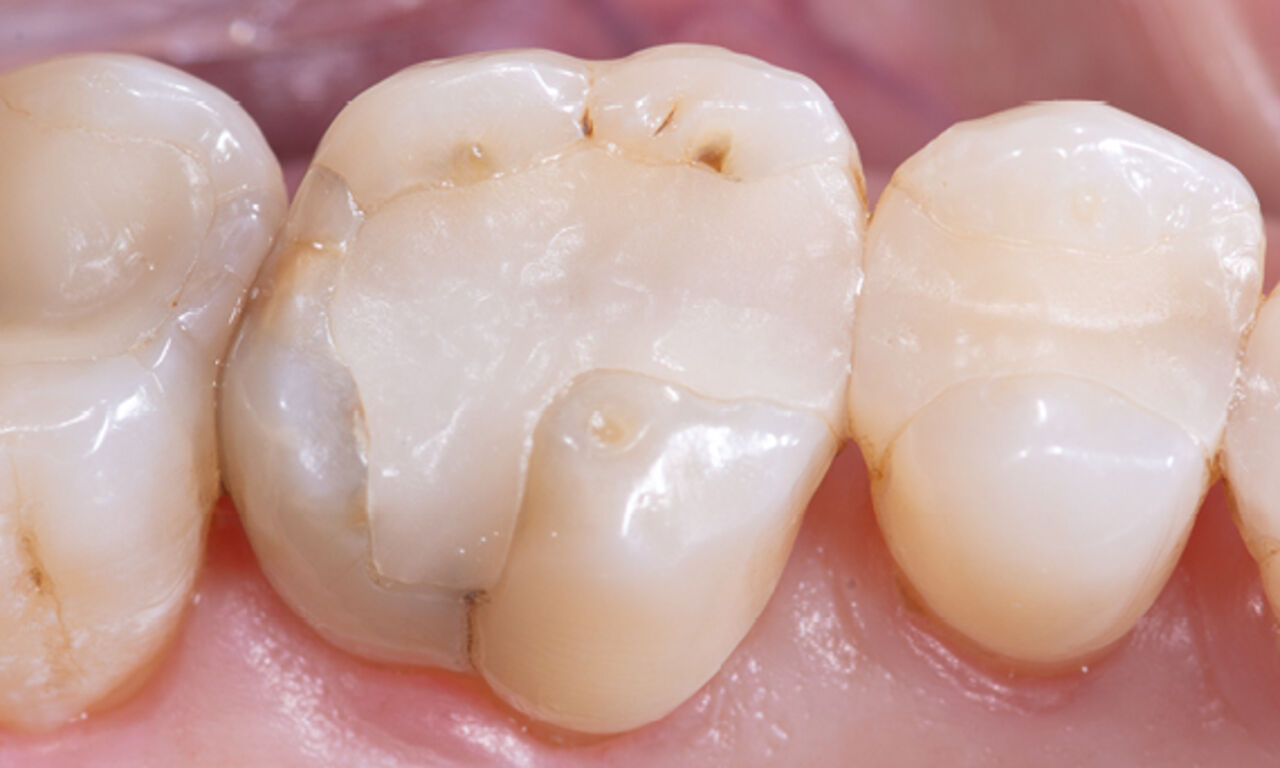

Before: Large insufficiency of the composite filling on tooth 16 with distal marginal ridge cracks, a lingual wall crack and distal recurrent decay.

After: Highly esthetic full-surface glass-ceramic crown.